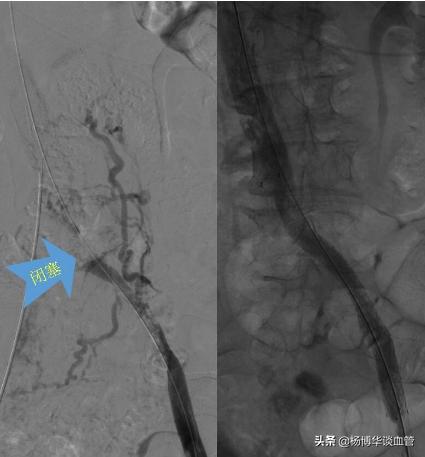

【病例 2】同样也是一位老太太,不同的是她是左侧大腿及小腿肿胀厉害,我们给老人做了检查后发现是髂静脉闭塞合并血栓,我们给予血栓抽吸术同时放了支架,术后下肢肿胀明显改善!(具体见下图)